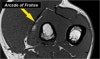

* Arcade of Frohse

The deep radial branches form the posterior interosseus nerve which penetrates the supinator muscle at the arcade of Frohse (arrow).